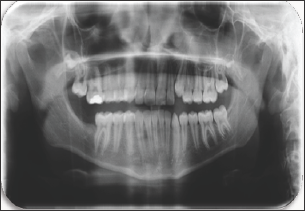

The case of erupted complex odontoma in mandibula was reported in this paper. The clinical and radiological examinations of a 12-year-old girl referred to the pediatric dentistry clinic with complaints of pain in the right mandibular region were performed. In the anamnesis taken from the patient, it was learned that she had no systemic disease. During her intraoral examination, a tooth-like tissue was observed inside of the gingiva in the right mandibular posterior region (Figure 1). No inflammation or ulceration was found in the mouth. During radiographic examination, it was observed that the patient's tooth number 47 was congenitally missing (Figure 2). The pre-diagnosis of complex odontoma was made after the clinical and radiological examinations. The patient was taken under an operation under local anesthesia and was operated with surgical procedures. As a result of the histopathological examination of the biopsy material obtained, the complex odontoma in opaque color with a dimension of 0.8x0.7x0.7 cm was confirmed (Figures 3-4).

Figure 4: Post-Operative Panoramic Film.